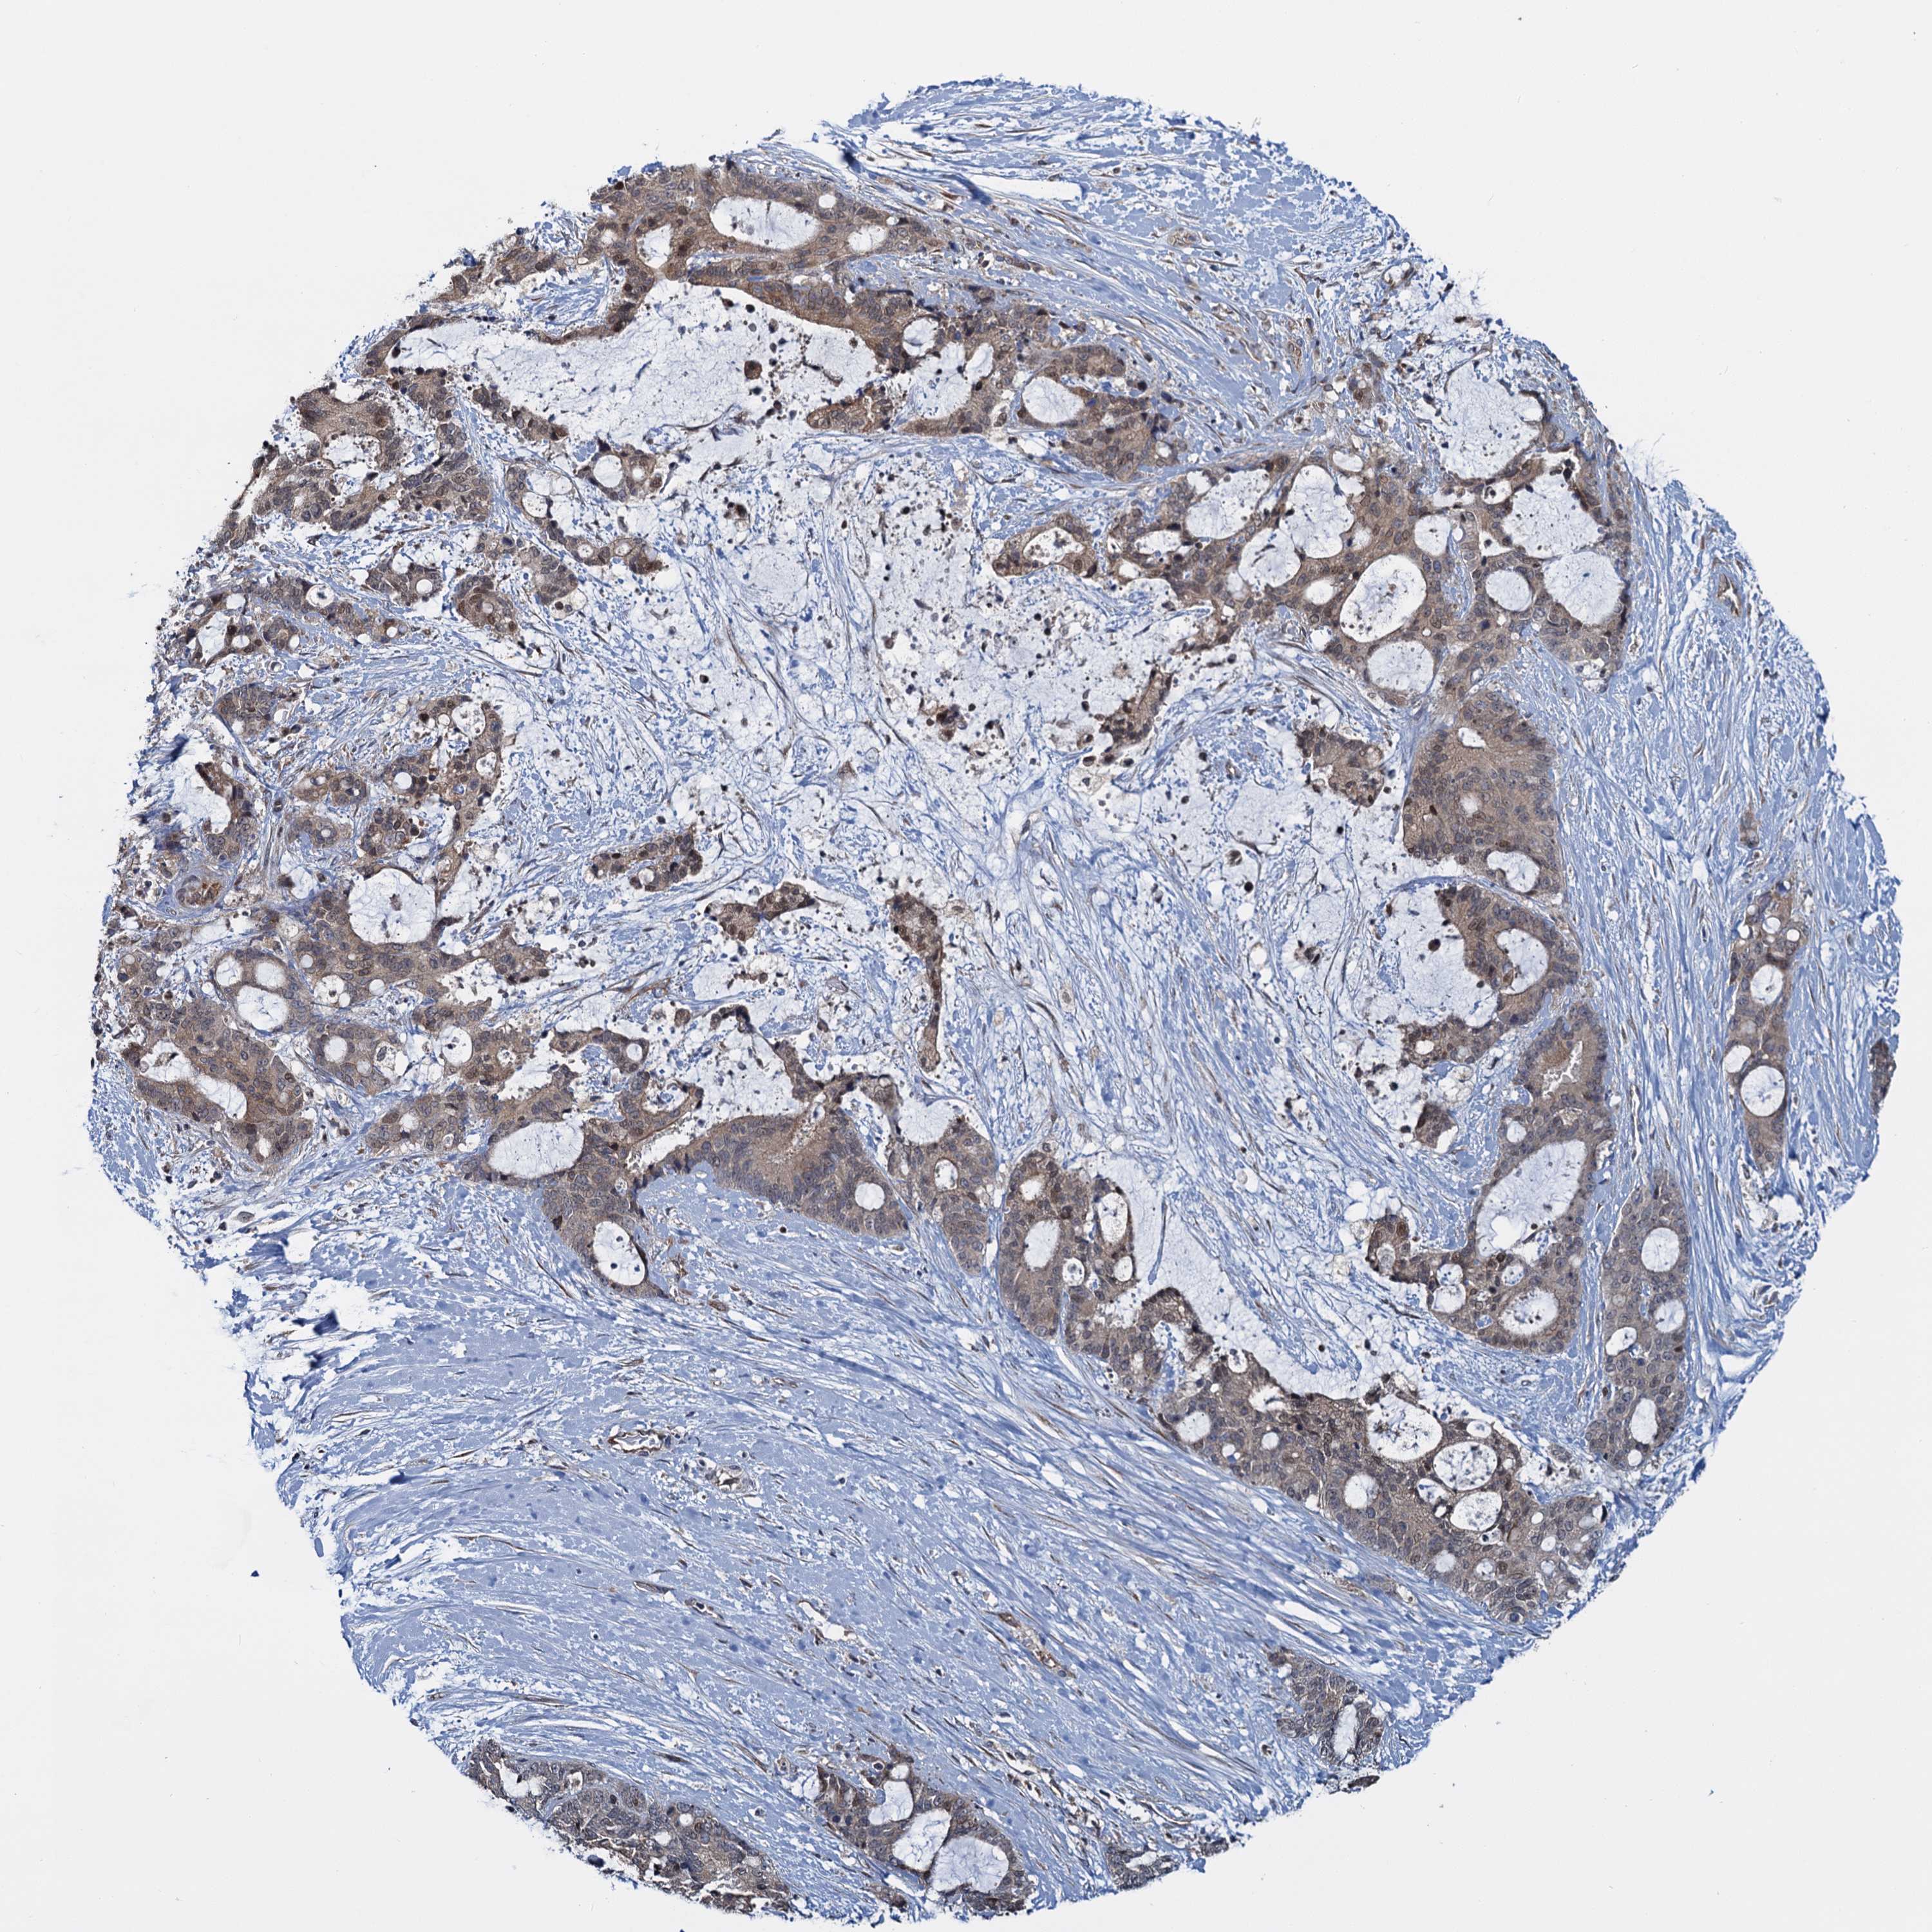

LIVER CANCER - Protein expressioni

A mouse-over function shows sample information and annotation data. Click on an image to view it in a full screen mode. Samples can be filtered based on level of antibody staining by selecting one or several of the following categories: high, medium, low and not detected. The assay and annotation is described here.

Note that samples used for immunohistochemistry by the Human Protein Atlas do not correspond to samples in the TCGA dataset.

Antibody stainingi

Antibody staining in the annotated cell types in the current human tissue is reported as not detected, low, medium, or high, based on conventional immunohistochemistry profiling in selected tissues. This score is based on the combination of the staining intensity and fraction of stained cells.

Each image is clickable and will lead to virtual microscopy that enables deeper exploration of all samples and also displays staining intensity scores, fraction scores and subcellular localization as well as patient and tissue information for each sample.

Antibody HPA041514

Staining

High

Medium

Low

Not detected

Intensity

Strong

Moderate

Weak

Negative

Quantity

>75%

75%-25%

<25%

None

Location

Nuclear

Cytoplasmic/membranous

Cytoplasmic/membranous,nuclear

Cholangiocarcinoma

Carcinoma, Hepatocellular, NOS